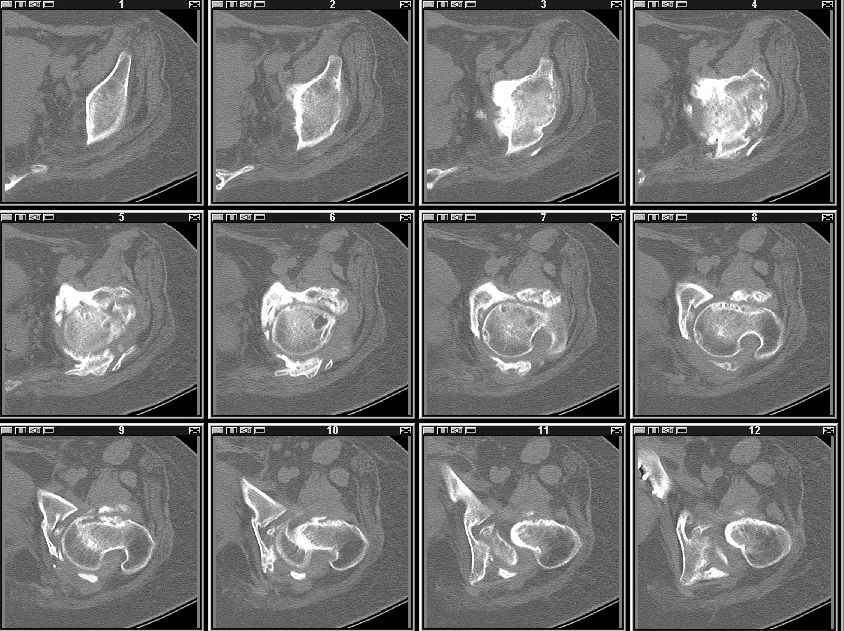

На сегодняшний день надо уточнить степень сращения впадины, величину дефекта, надо делать кт шаг 2-3мм не больше. Если сращения нет - отдельная песня.

высылаю КТ